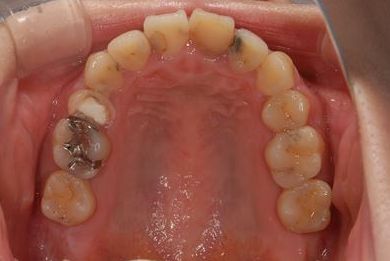

治療前

• 治療前